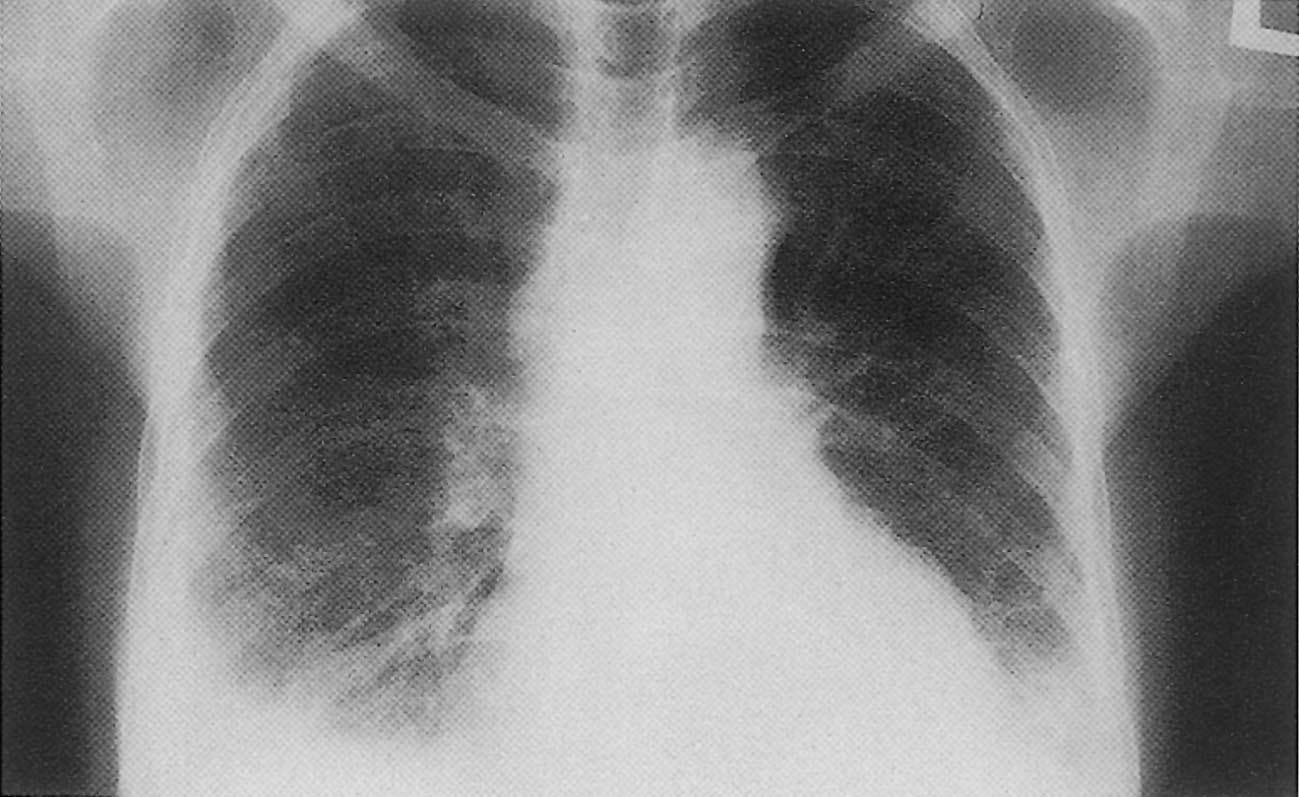

أولا : يوجد حالة تتجمع بها المياه بين القفص الصدري والرئتين ويطلق عليه الفراغ البلوري، ويتم اكتشاف الحالة عن طريق التصوير الشعاعي وتكون معالجتها بسيطة

- تصوير الصدر بالأشعة السينية وذلكم ليتمكن الطبيب من مشاهدة السوائل على الرئة.